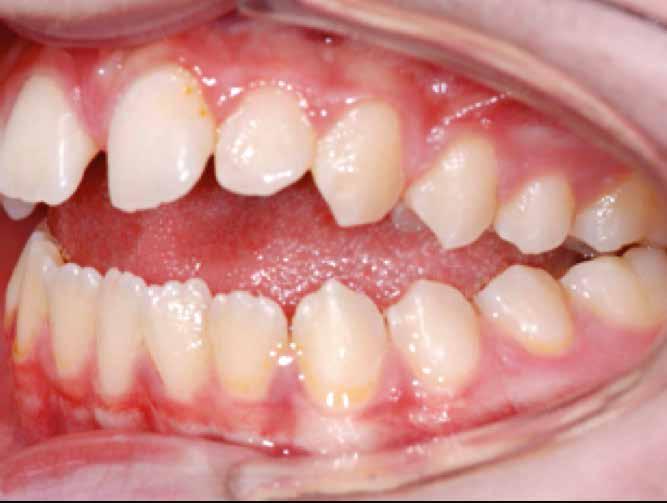

Lány páciensem I. fázisú kezelését 10 évesen kezdtük el bimaxilláris funkciós, kivehető készülékkel. Megfigyelhetőek a class 2-es eltérésnél tipikusan jellemző szűk felső és alsó fo-

gívek, valamint a nagy overjet, a mandibula disztál helyzete, továbbá a felső metszőfogak protrúziója, amelynek kialakulásához sokszor hozzájárul az ujjszopás is (1-3. képek)

A vegyes fogazati kezelési célok a fogívek tágítása és a mandibula meziális irányú növekedésének a biztosítása volt. Fontos, hogy az ilyen típusú készülékeket nem csak éjszaka, hanem napközben is – amennyit csak lehet – hordani kell a minél hatékonyabb működés érdekében. A 18 hónapos első fázisú kezelésnek köszönhetően az alap kezelési célok megvalósultak, sikerült a class 1-es okklúziót beállítani (4-7. képek).